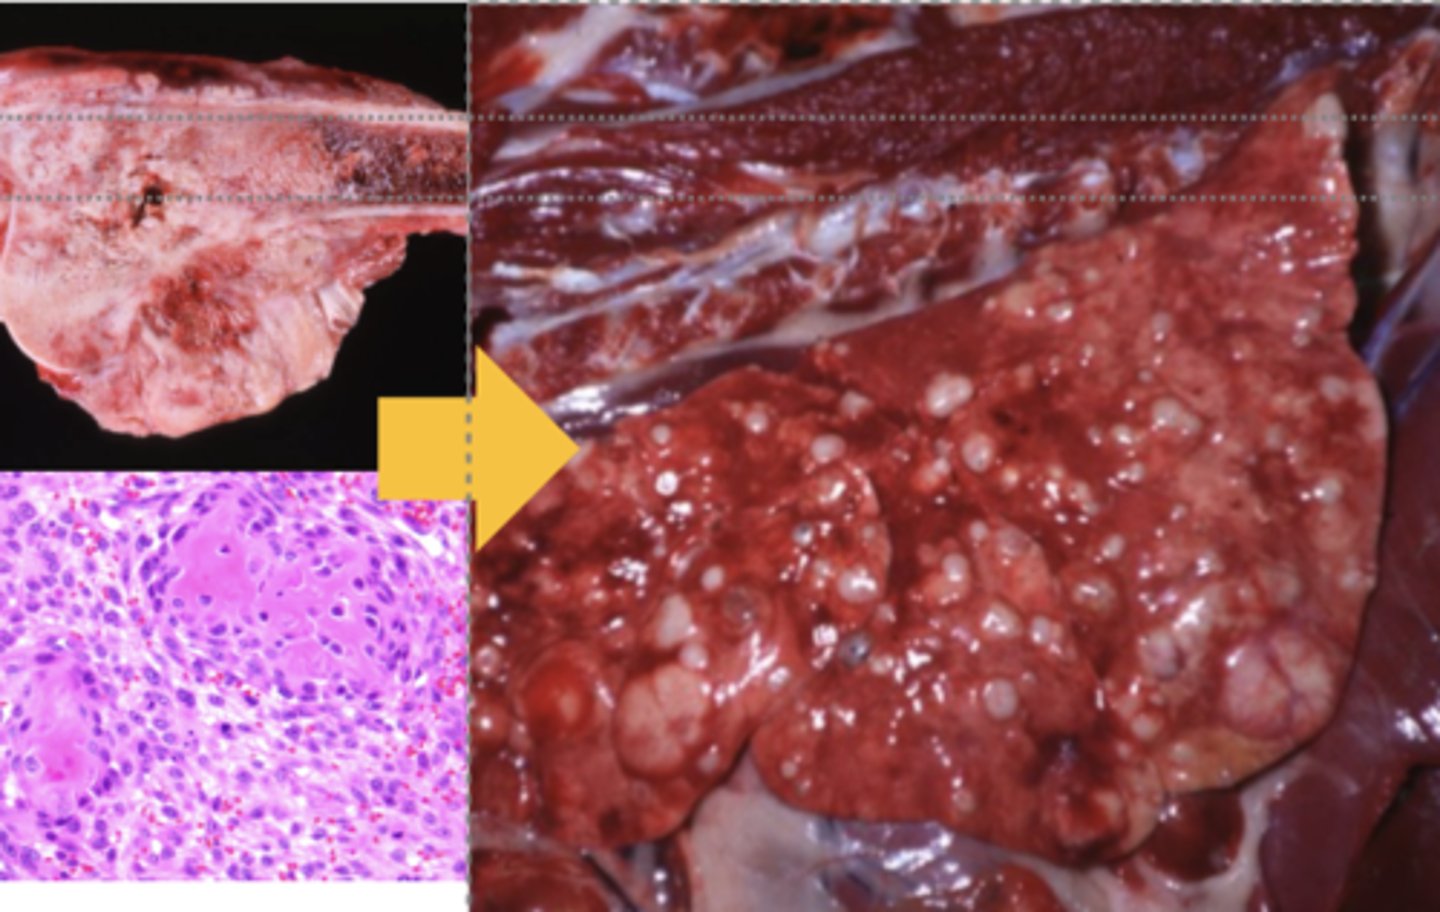

BLV Lymphoma

-nodular

What has caused this gross appearance of this bovine liver?

Metastatic tumor

What kind of tumor is this? (broad category)

Hematogenous metastasis

What kind of tumor is this? (broad category)